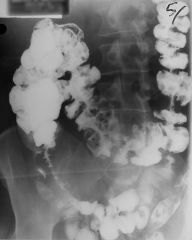

Barium enema showing diverticular disease

Cobblestone appearance of colon

characteristic of Crohns

Kantours string sign